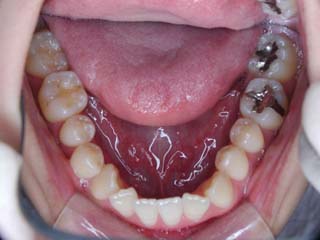

主訴:上の歯が出ている

診断名:顎関節症、上顎前突、叢生を伴う開咬

年齢:20歳

使用した主な装置名:TPB、マルチブラケット装置

抜歯/非抜歯および抜歯部位:抜歯(上顎左右第一小臼歯、下顎左右第二小臼歯)

治療期間:動的処置2年3か月、経過観察3年

費用の目安:保険適応 自己負担金として30~50万

リスク、副作用:外科手術によるリスク、マルチブラケット治療に伴う歯根吸収など偶発症が発生するリスクがある。

比較的強い叢生と、下顎の劣成長を伴う開咬が見られます。成長を終了した永久歯列ですので、骨の大きさのズレへのアプローチは大きく別れる所です。程度が小さければ、歯の傾きで補うように解決しますし、大きなズレであれば、外科的に骨のズレを改善する治療が選択されます。垂直的な問題はその他の不正咬合と比較して、解決が極めて困難な事が多いです。治療後の後戻りが頻繁に見られる不正咬合ですので、外科矯正での改善が望ましい場合も多いでしょう。

術前矯正の仕上げにスプリント治療を行った方が良い場合が多いです。現在、当院での治療では、術前に3か月のスプリント治療を必須にしております。せっかく手術までしてかみ合わせの位置を合わせようとしているのに、顎の関節の位置がずれていたらどうなるでしょう。顎の関節は往々にして顎の大きさのズレをカムフラージュするような偏位を示すので、術後にじわじわと後戻りしているような現れ方で、ズレが見えてくるのでは?このスプリント治療を徹底できたケースでは術後の安定性が極めて高いと感じています。

外科手術は、上顎のインパクションのみをLeFort1にて行いました。